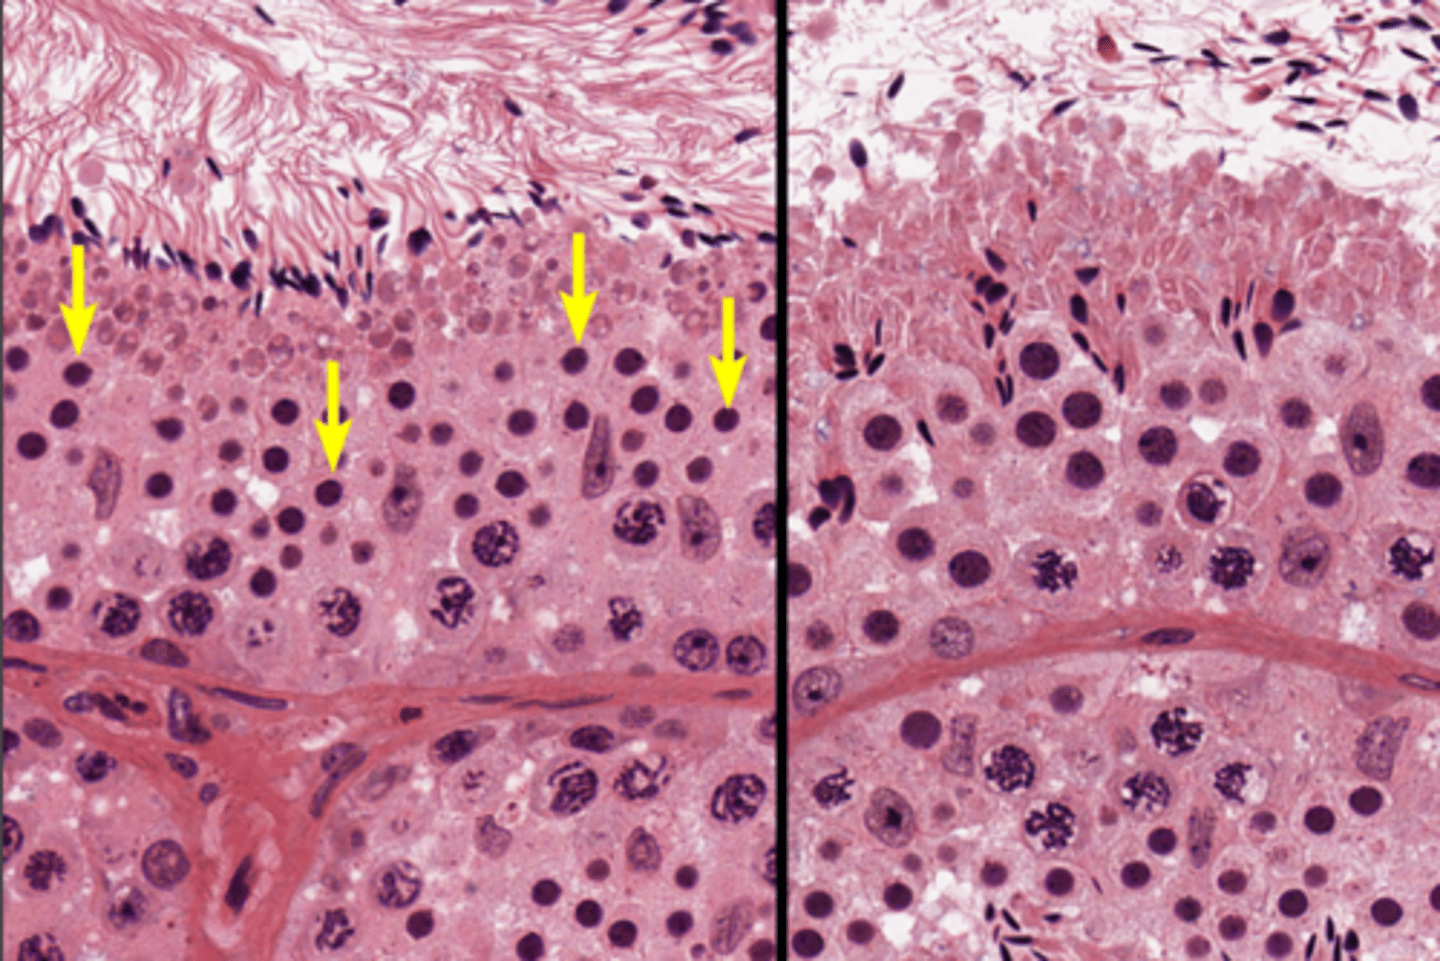

Seminiferous tubules

Seminiferous tubules

Seminiferous tubules

Spermatogenesis

Spermatogenesis

Spermatogonia

Primary spermatocyte

Spermatogonia

Spermatid (early)

Primary spermatocyte

Spermatid (late)

Spermatid (early)

Spermatozoon

Spermatid (late)

Spermatozoa